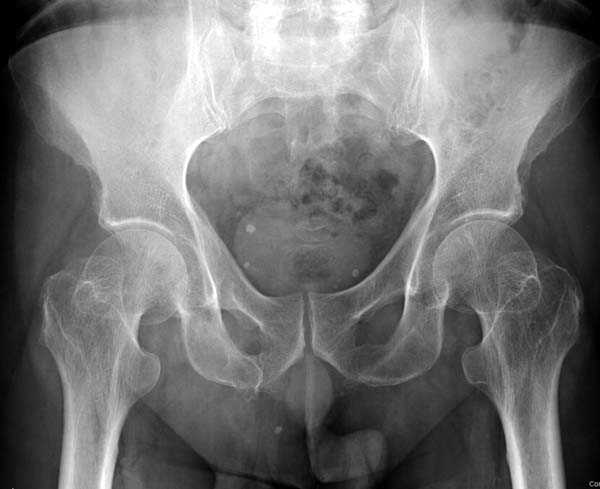

Уважаемые коллеги,

Хотели бы знать тактику лечения 62 летнего больного, отягощенного

алкоголизмом, с жалобами на боли в правом тазобедренном суставе.

Не смогли добиться вразумительного ответа по поводу анамнеза травмы,

клинически движения ограничены из-за боли, сделанные снимки сустава

представлены. На КТ неполный перелом шейки. Начали профилактику

возможного Алкогольного Делирия.

Дальнейшее рекомендации, оставить как есть, или профилактическая

перкутанная фиксация?